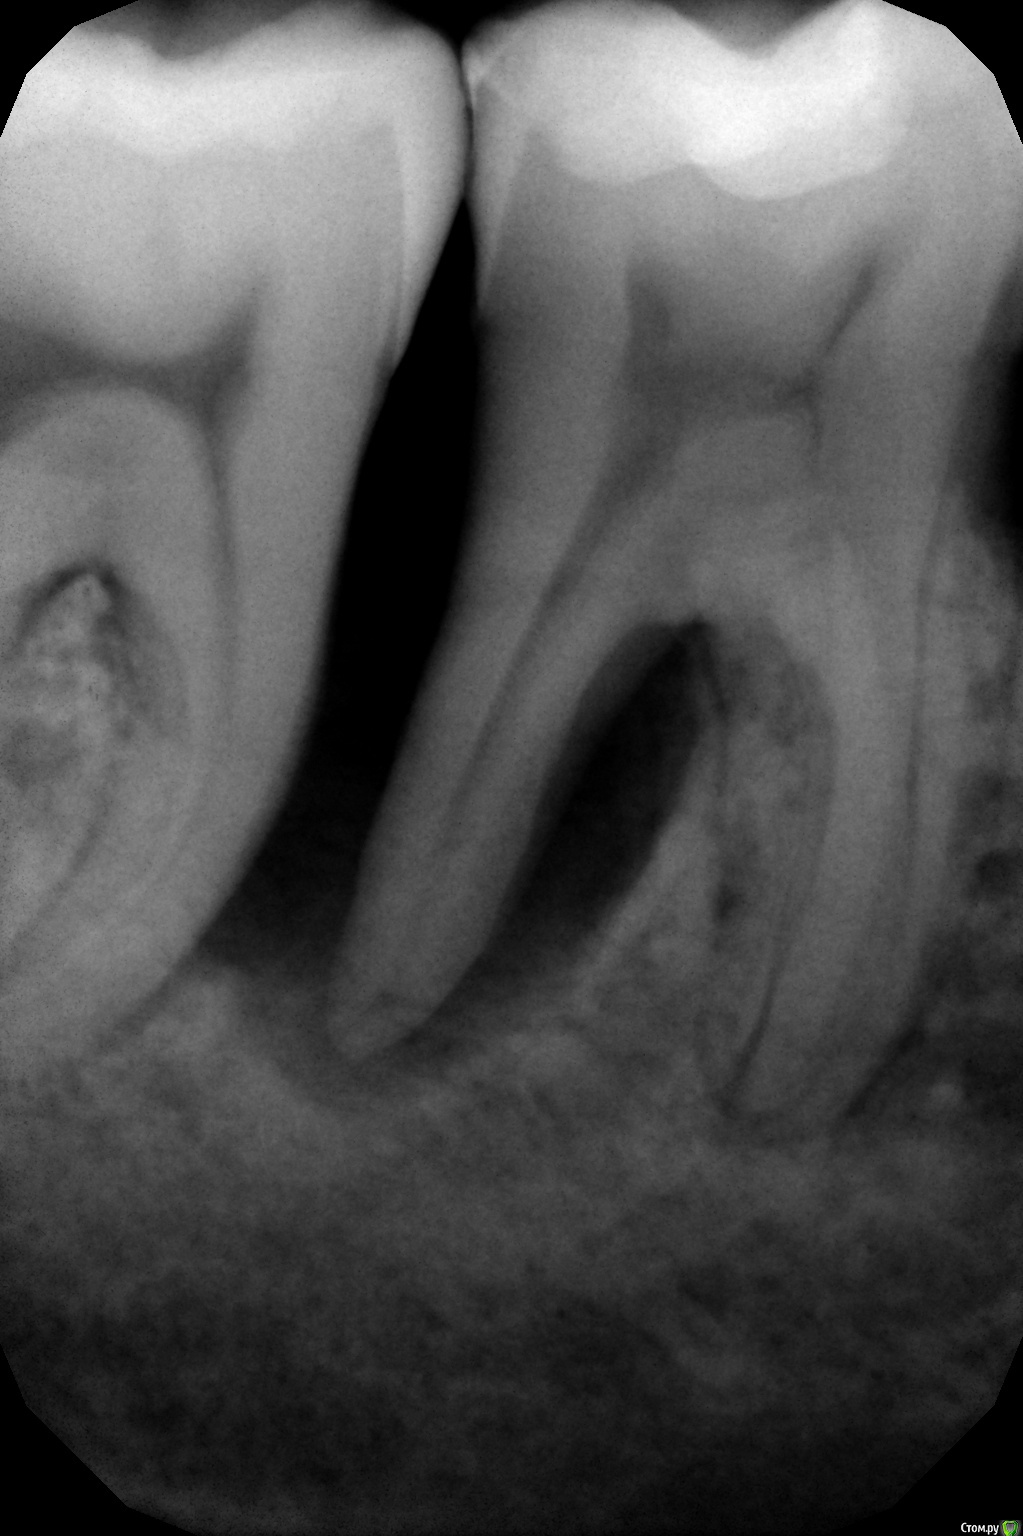

Muhamedgaliev Опубликовано 29 июля, 2019 Автор Поделиться Опубликовано 29 июля, 2019 Уважаемые коллеги. Подскажите, тактику лечения в данном клиническом случае.В полости рта все спокойно, проведен кюретаж, полировка корня, слизистая бледно розового цвета. Ссылка на комментарий

dentikl Опубликовано 29 июля, 2019 Поделиться Опубликовано 29 июля, 2019 Уважаемые коллеги. Подскажите, тактику лечения в данном клиническом случае.кт и если очаг подтвердится-удаление Ссылка на комментарий

___49___ Опубликовано 29 июля, 2019 Поделиться Опубликовано 29 июля, 2019 как из вариантов - гемисекция, но нужно больше данных . 1 Ссылка на комментарий

DmitrySH Опубликовано 30 июля, 2019 Поделиться Опубликовано 30 июля, 2019 . А потом убрать "остатки", если себя не оправдают, и заимплантировать.. Эти полумеры с гемисекцией будут иметь достаточно сомнительные перспективы. Если брать во внимание финансовую сторону вопроса, то лучше один раз поставить 2 импланта. 1 Ссылка на комментарий

Павел7809 Опубликовано 9 августа, 2019 Поделиться Опубликовано 9 августа, 2019 я бы больше за соседний зуб беспокоился, можно и его потерять. Ну а тут удаление... Ссылка на комментарий